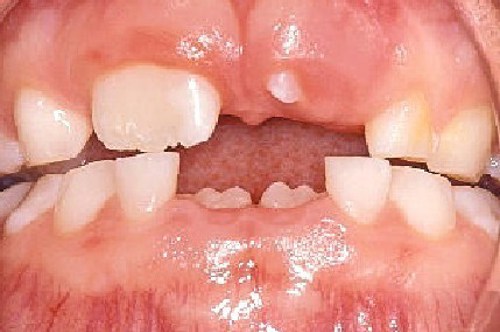

Det andet viser 6-årstanden der dukker op bagved den bagerste mælketand.